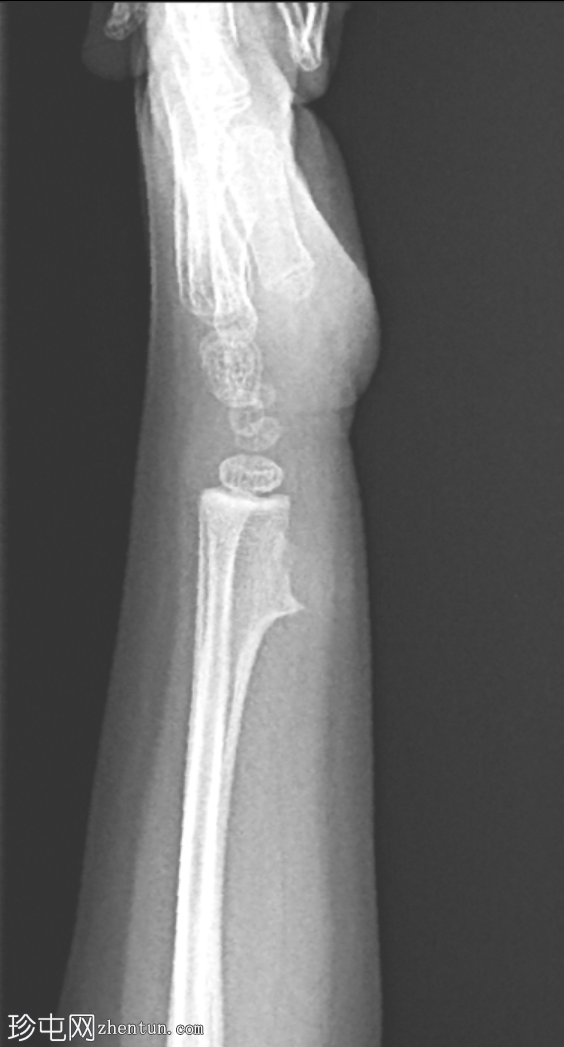

X线片

侧位片

可见桡骨远端干骺端前外侧有一骨性增生。病变与母骨皮质和髓质相连。边界清晰。无皮质破损、骨膜反应及相关软组织肿块。邻近尺骨外观正常。无骨折或脱位。